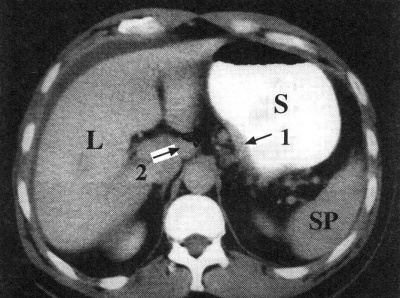

טומוגרפיה ממוחשבת - מאפשרת להדגים את גודל השאת, התפשטותה לאיברים סמוכים, בלוטות לימפה מוגדלות או גרורות לאיברים אחרים (תצלומים 21.3-18.3). ב-CT הדיוק באבחנת T4 הוא 90% וב-T1 הוא 23%.